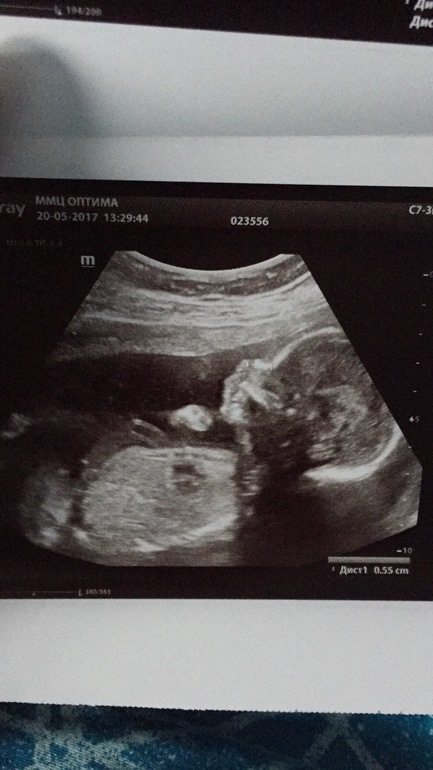

Вот я и дождалась 2 скриннинга. Так быстро летит время. Пошла рано в платную клинику. Стоимость 1300. Все показали и рассказали моего сыночка. Мой сладенький мальчик. Кувыркался в итоге , что бы посмотреть и намерить заняло час, час 20. Была с мужем. Счастлив как слон. Патологий не выявили. Тьфу тьфу тьфу. Кто ещё мне будет говорит что после зб нельзя сразу беременеть, посмотрите на это чудо. Целый день маму пинает и мстит за то что потревожили. Фото УЗИ подкат.

О, поздравляю! На первом фото ручку у ротика держит))) Тоже жду свой скрининг на днях.